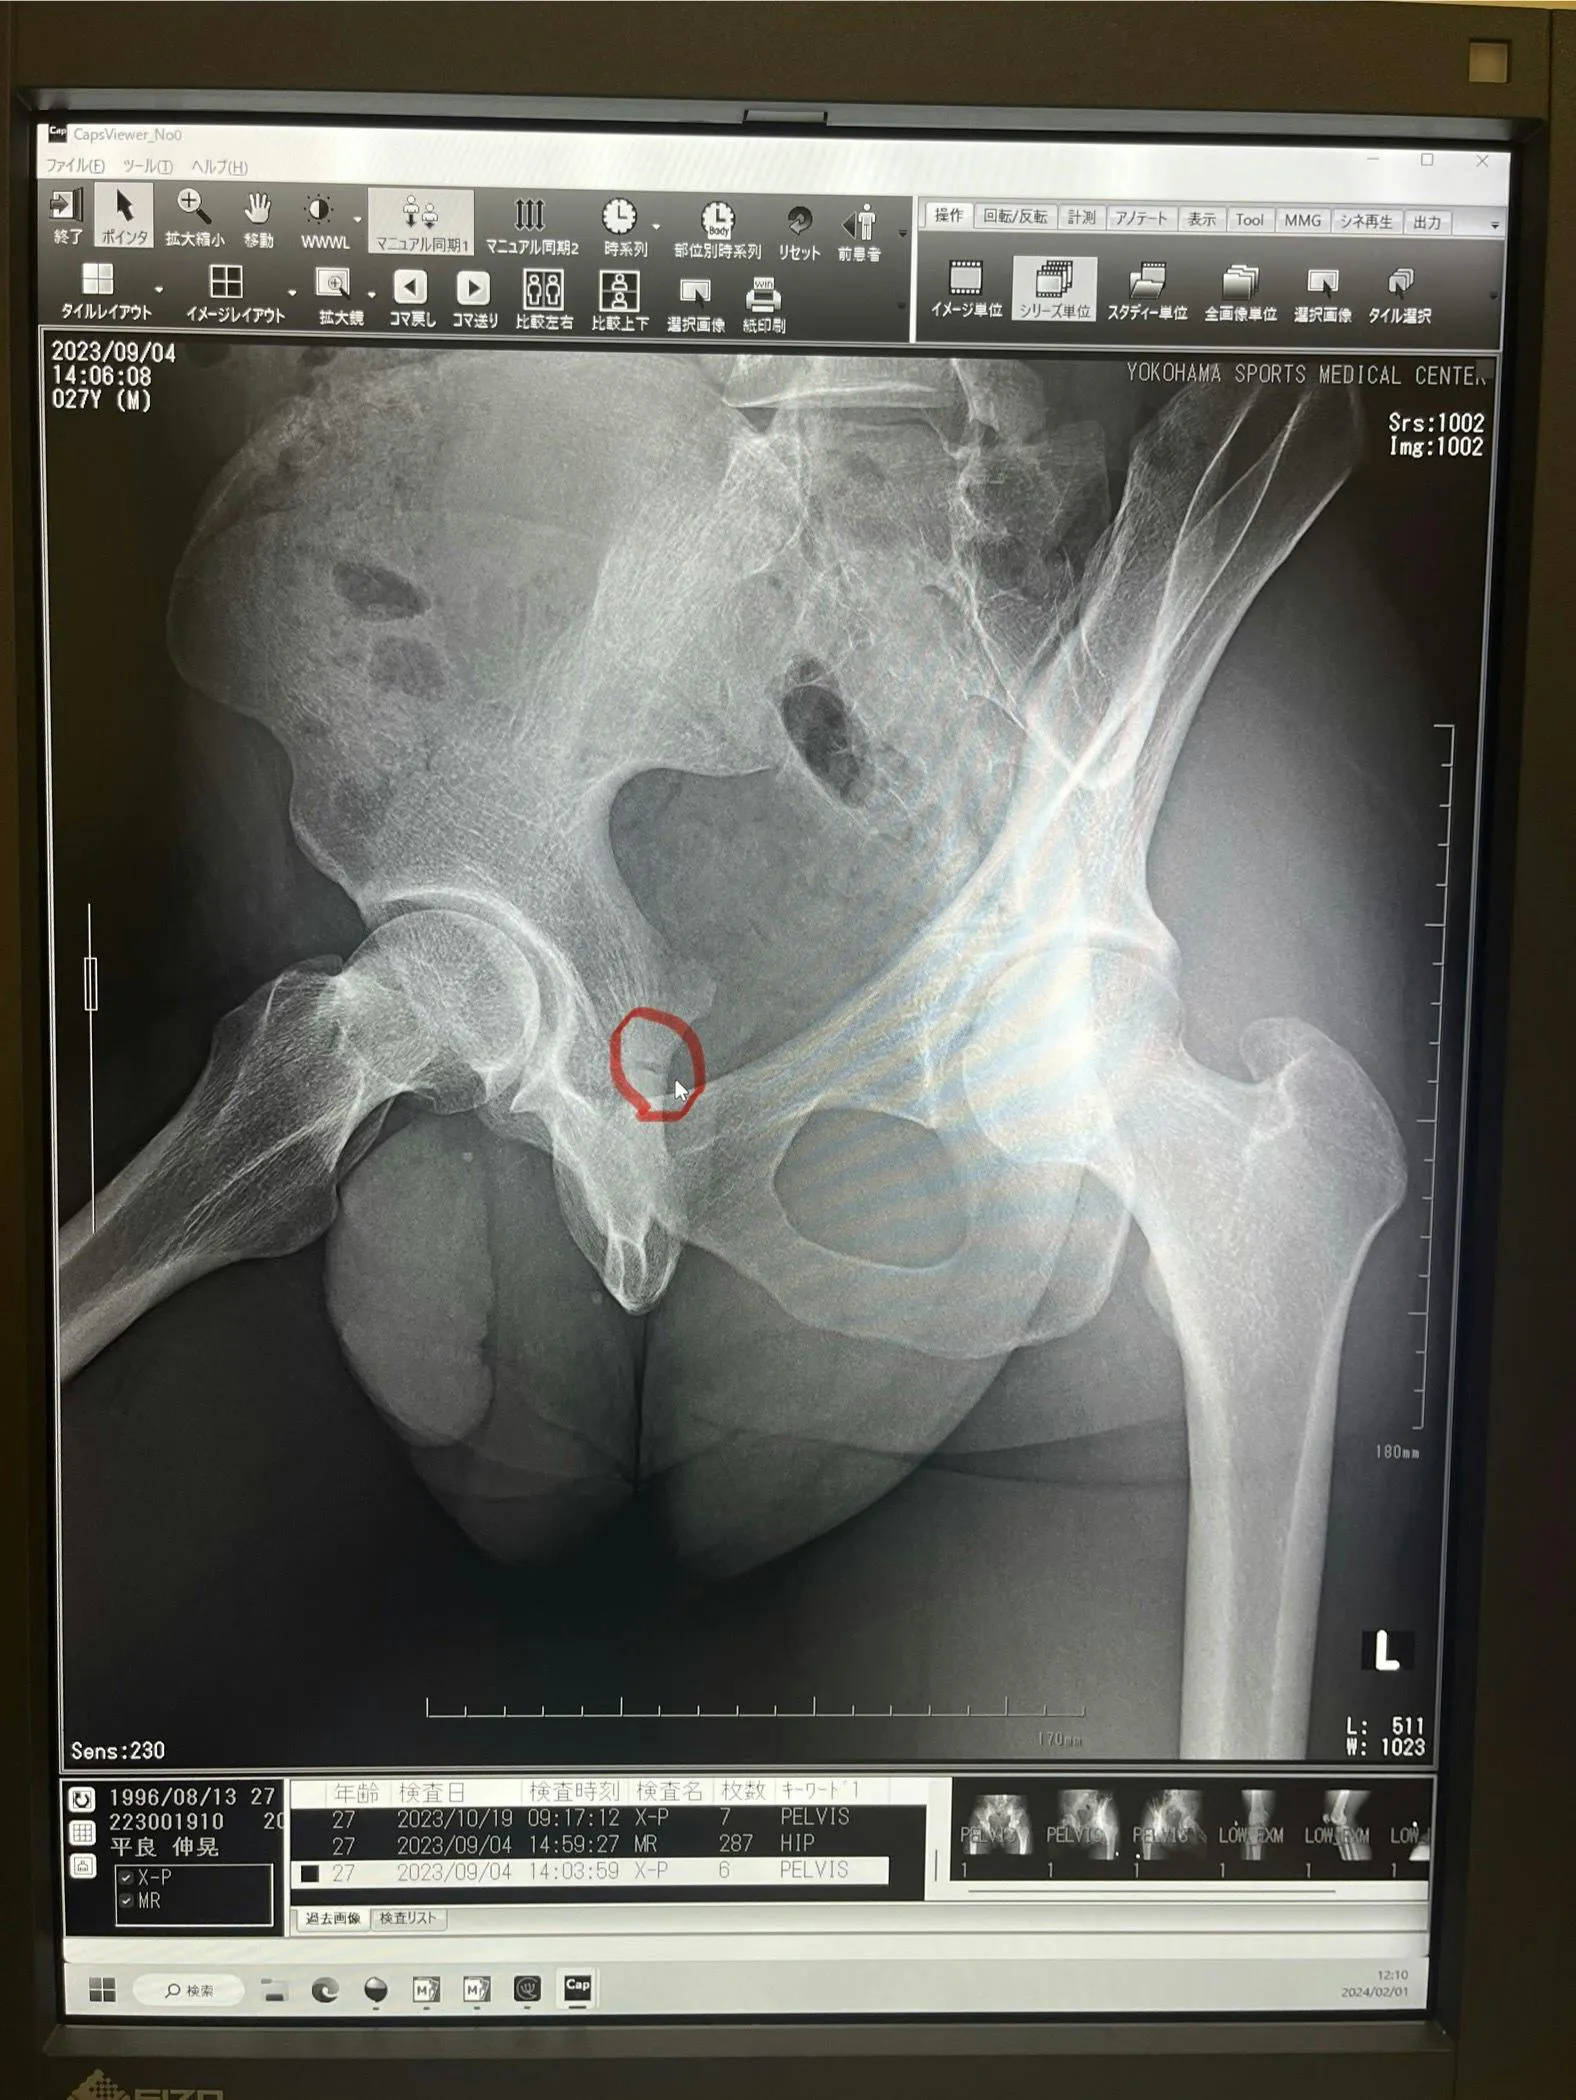

痛みはそこまで強くなかったので、我慢すればプレー出来る、そうしながらプレーを続けた結果、パフォーマンスも落ち、そのシーズンの結果も芳しくなく、2023年9月、右坐骨疲労骨折と診断を受けました。

怪我を診て下さった担当の先生からは「この場所を骨折してる人は人生で初めて見た、いつ頃骨がくっつくのかも判断が難しい」と言われ、お尻のかなり奥の部分を骨折していたため、競技に復帰をするのであれば手術はせずにリハビリと適切な栄養をとって保存療法を行う方が良いという事で回復に努めました。

怪我した当時の写真、分かりにくいかもしれませんが、カーソル付近にある隙間が骨折箇所です。